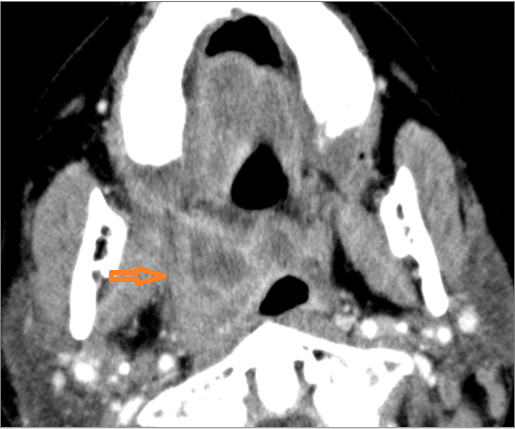

There is suppurative retropharyngeal lymphadenopathy. [Yes/No]

If there is suppurative retropharyngeal adenopathy what is the maximum short axis dimension of the largest suppurative node. MEASUREMENT [Yes/No]

There is related edema/abscess within the adjacent parapharyngeal/retropharyngeal spaces. [Yes/No]